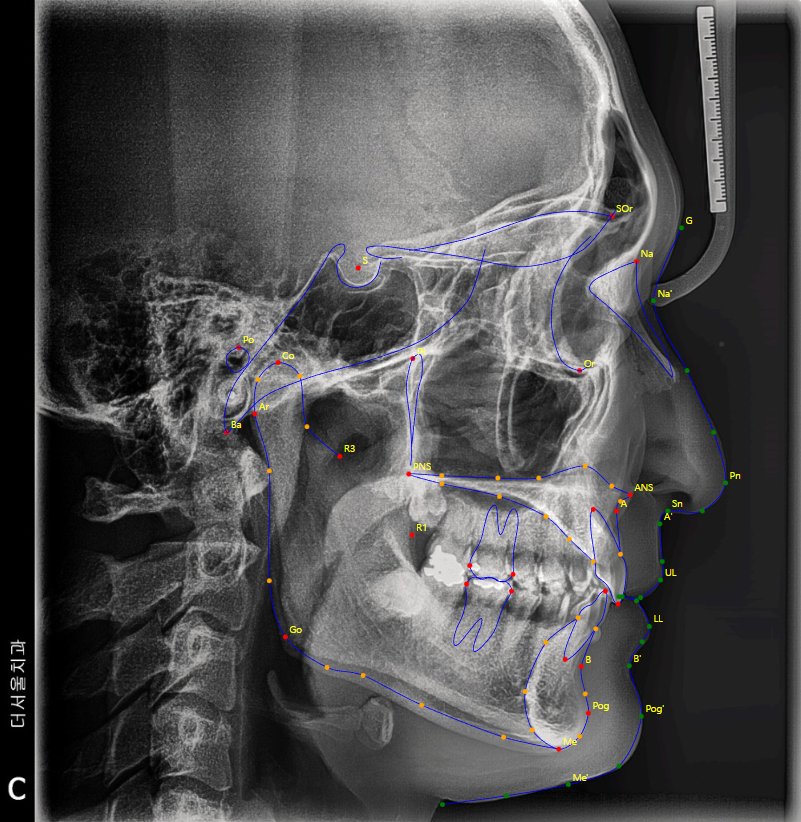

앞서 보여드린 사진에서,

두부 방사선 측면 사진(Ceph) 이 있었죠?

거기에 가상의 지표를 찍게 됩니다.

cephalometric bony landmark 라 부르는데,

사진으로 보여드리겠습니다.

이렇게, 해부학적 요소에 따라서

랜드마크를 찍어서 발치를 해야 되는지

브라켓은 어디에 붙여야 되는지 등을

알 수 있습니다.

저는 여기서, 코 끝과 턱 끝을 이은

‘심미선’ 이라 부르는 리케츠 라인을 주로 봅니다.

이 선을 기준으로, 입술이 튀어나와있다면

‘돌출입’ 그렇지 않다면 ‘정상’ 의 범주로 보며

발치 결정의 기준점이 될 때도 있습니다.